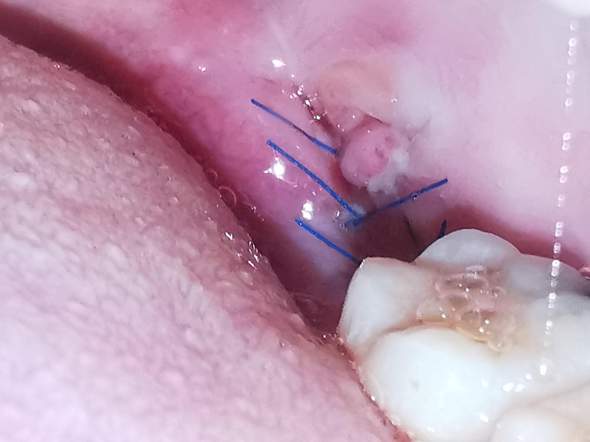

Ist Meine Zahnwunde In Ordnung Entzundung Zahnarzt Zahnfleisch

Zahn Nahttechniken Und Materialien Fur Die Oralchirurgie